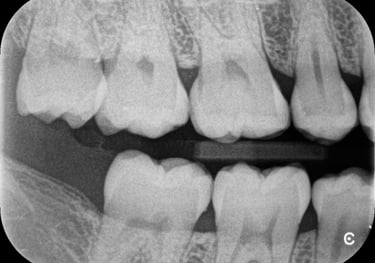

RADIOGRAFIA INTERPROXIMAL